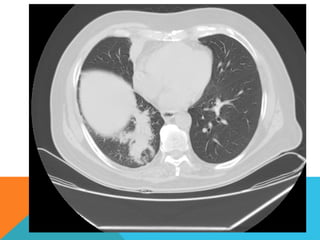

ABORDAJE TÉCNICO: Se realiza estudio con ventana mediastinal y de parénquima pulmonar con técnica de ALTA

RESOLUCION, en inspiración y espiración, mediante  cortes axiales, desde ápices hasta bases pulmonares, con las

siguientes observaciones

Ambos pulmones con neumatización conservada, con sobredistensión pulmonar, y áreas de atrapamiento aéreo,

bilateral con cambios fibrosos cicatriciales apicales derechos. Se demuestran áreas de condensación en topografía

predominantemente parenquimatosa pulmonar derecha, la mayor de ellas evidenciada hacia la base, acompañada

de broncograma aéreo, la medición máxima al corte axial de 6.1 por 2.2 cm, en topografía del segmento posterior

del lóbulo inferior, S10 así como también otra más se definen topografía de similares características en topografía

del segmento medial del lóbulo medio, S5. En topografía parenquimatosa pulmonar izquierda imagen de similares

características a las ya descritas en topografía del segmento lingular inferior, S4.

El corazón de dimensiones conservada, de contornos regulares, sin desplazamientos; en la región hiliar derecha se

define adenopatía de medición máxima corte axial de 1.6 por 1.4 cm.

ABORDAJE TÉCNICO: Serealiza estudio con ventana mediastinal y de parénquima pulmonar con técnica de ALTA RESOLUCION, en inspiración y espiración, mediante  cortes axiales, desde ápices hasta bases pulmonares, con las siguientes observaciones En las partes blandas y las estructuras óseas dentro de los límites de la normalidad. Las regiones axilares libres. Ambos pulmones con neumatización conservada, con sobredistensión pulmonar, y áreas de atrapamiento aéreo, bilateral con cambios fibrosos cicatriciales apicales derechos. Se demuestran áreas de condensación en topografía predominantemente parenquimatosa pulmonar derecha, la mayor de ellas evidenciada hacia la base, acompañada de broncograma aéreo, la medición máxima al corte axial de 6.1 por 2.2 cm, en topografía del segmento posterior del lóbulo inferior, S10 así como también otra más se definen topografía de similares características en topografía del segmento medial del lóbulo medio, S5. En topografía parenquimatosa pulmonar izquierda imagen de similares características a las ya descritas en topografía del segmento lingular inferior, S4. No hay derrame ni áreas de engrosamiento pleurales. El patrón vascular es de características normales donde no se delimitan imágenes de lesiones aneurismáticas únicamente cambios por aortoesclerosis incipiente. El corazón de dimensiones conservada, de contornos regulares, sin desplazamientos; en la región hiliar derecha se define adenopatía de medición máxima corte axial de 1.6 por 1.4 cm.

El estudio radiológicosimple evidencia una lesión nodular menor del centímetro, radiodensa, caracterizada como granuloma cálcico. En mi opinión el estudio de TCAR fue realizado por ese motivo y ello permito identificar los hallazgos “floridos” que ya se señalan y se muestran en las imagen axiales ya seleccionadas.